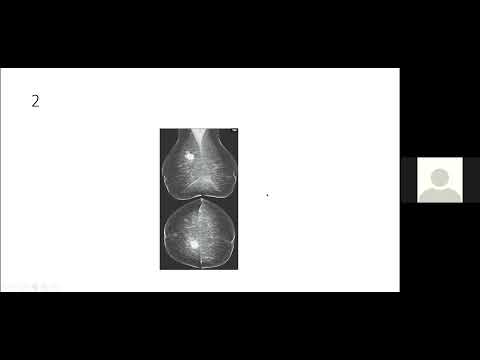

TEAM FRCR 2B GU & Mammogram Viva practice

TEAM FRCR 2B Viva Practice Session (MSK, GU & Breast Modules Revision). 12th December, 2020.